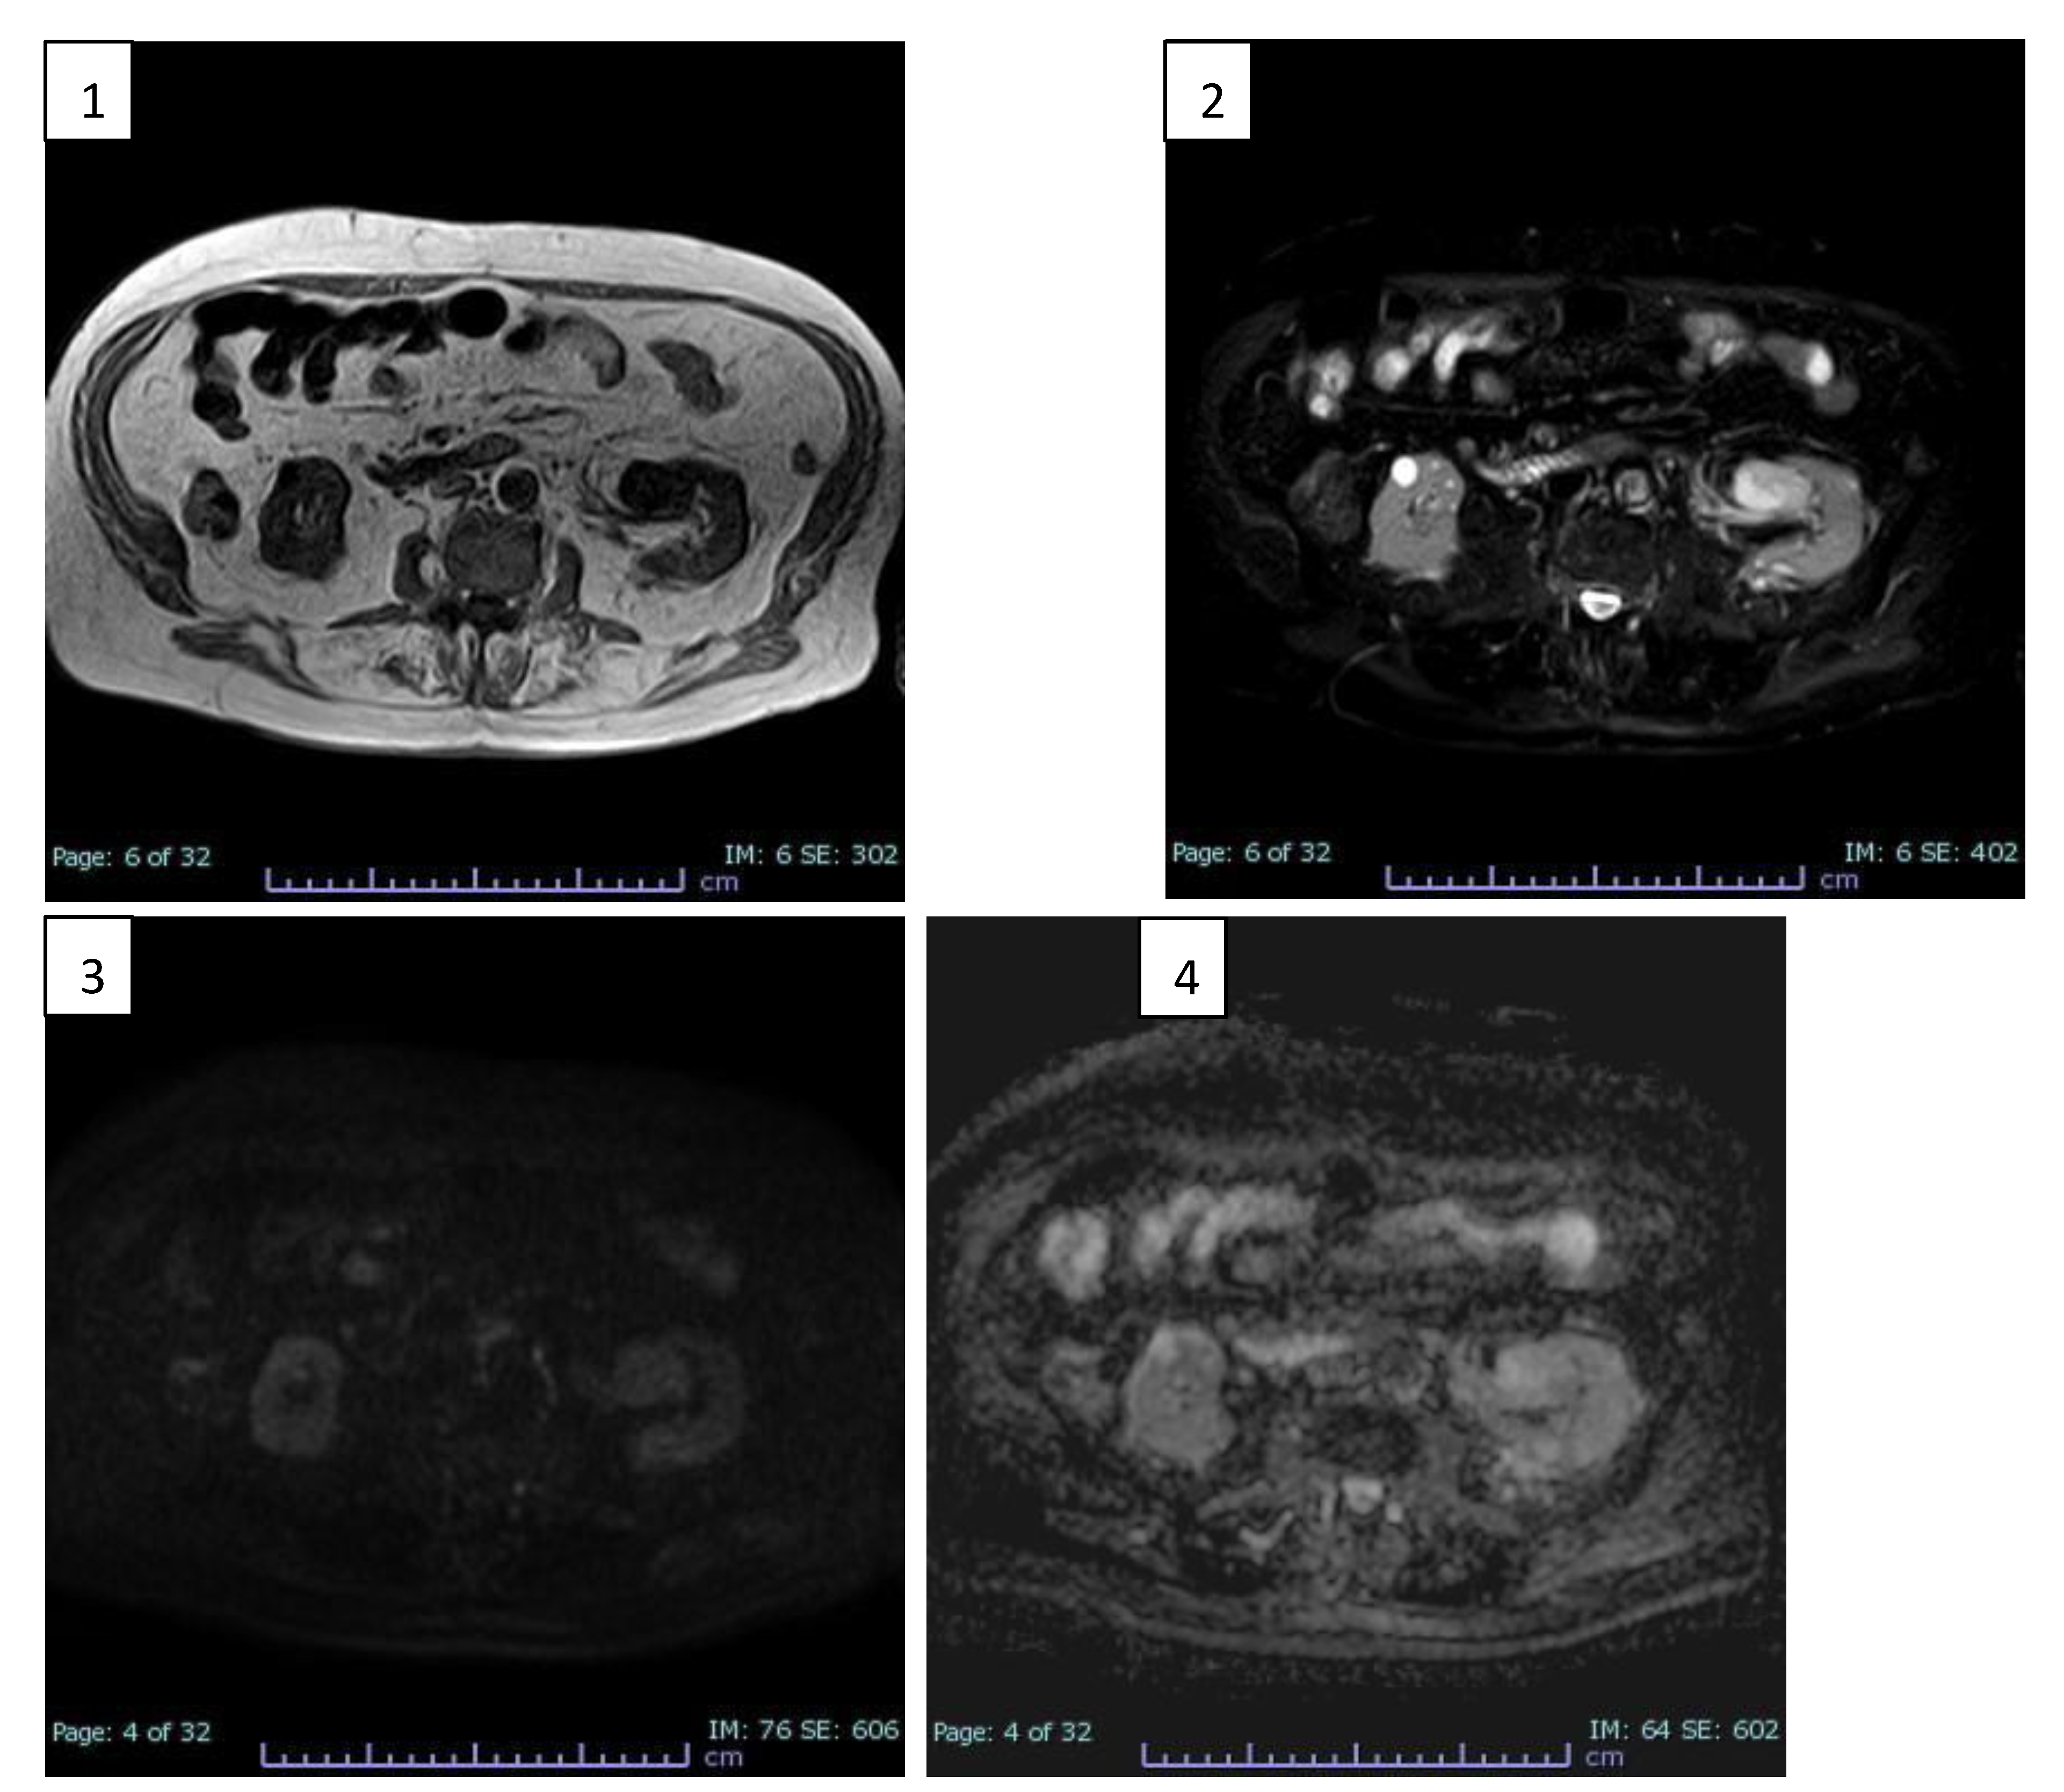

Following this finding, he underwent CT investigation without and with intravenous CM (Figure 1).

An axial CT scan showed an expansive formation with oval morphology in the left renal sinus outlining the organ with dimensions of about 32 x 30 mm, which tended to grow in the connective tissue of the renal sinus, slightly dislocating the inferior calyx group.

In non-enhanced acquisition (Figure 1.1) this formation presented a heterogeneous appearance with average values of HU of 19-20 HU, with negative values with adipose significance in some places, and peripheral areas values of 37-60 HU.

In the arterial phase scans (Figure 1.2), the periphery of the lesion showed a clearly annular and pseudonodular enhancement with a tendency to centripetal filling and densitometric values reaching 230 HU, thus demonstrating a highly representation of vascular tissue component.

In the venous phase (Figure 1.3), the lesion showed a tendency to homogeneous filling with average values up to 130 HU. The lesion showed homogeneously persistent enhancement in late scans (Figure 1.4) with HU values between 50 and 70.

Neither calico-pyelic dilatation was evident nor significant lymphadenopathy in the mesenteric, para-aortic and retroperitoneal stations.

The imaging features reported in the case presentation show a tendency towards heterogeneity, indeed, both methods lean towards a pre-operative diagnosis of malignant lesions. At the CT scan without CM, an inhomogeneous hypointense lesion is evident in the left renal pelvis, at the level of the lower third, which shows uneven density in all its points, varying from punctiform areas with adipose-like densitometric coefficients (from -10 HU to -2 HU), to more frankly solid areas (49-20 HU) and to sections suggesting the presence of vascular components (37-60 HU). These findings are confirmed in subsequent scans enhanced with CM and, in particular, the lesion shows a frank enhancement in the more caudal peripheral portion in the arterial phase (up to 230 HU). In the subsequent portal phase a more homogeneous contrastographic filling of the entire lesion, with values of around 130 HU, was noted confirming the presence of an important hypervascular tissue component.

However, the lesion shows no frank signs of invasiveness or compression of the surrounding structures, in the absence of dilation upstream and downstream of the lesion. Furthermore, there are no signs of necrosis or calcifications within the lesion.

Figure 1. CT scans before and after enhancing with CM. 1) Non enhanced axial CT scan: a hypodense expansive formation is seen in left renal sinus (32 x 30 mm). 2) Axial CT with CM early arterial phase: the formation shows peripheral annular and pseudonodular enhancement. 3) Axial CT with CM venous phase: the formation shows tendency to homogeneous filling. 4) Axial CT whit CM late phase: the formation shows homogeneously persistent enhancement.